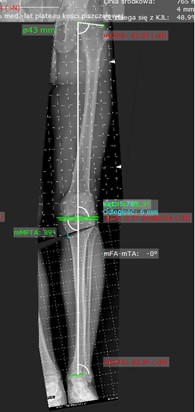

Zrozumienie mechanizmu działania osteotomii wymaga najpierw poznania pojęcia osi mechanicznej kończyny. U osoby z prawidłowym ustawieniem osi kończyny dolnej, oś mechaniczna – czyli linia łącząca środek stawu biodrowego ze środkiem stawu skokowego – przebiega przez środek stawu kolanowego. To gwarantuje równomierne obciążenie stawu. Rysunek 1.Jednak u pacjentów z szpotawością (ustawienie szpotawe, łac.genu varus) ta oś przesuwa się przyśrodkowo, co prowadzi do nadmiernego obciążenia przyśrodkowego przedziału stawu kolanowego lub w przypadku koślawości (ustawienie koślawe, łac. genu valgus) oś przesuwa się w kierunku bocznym, co nadmiernie obciąża przedział boczny kolana. Nadmierne obciążenia prowadzą do rozwoju zmian zwyrodnieniowych.

Aby móc określić wskazania do zabiegu, konieczne jest wykonanie zdjęcia radiologicznego posturalnego, które obejmuje na jednej kliszy stawy kończyny dolnej w pozycji stojącej. Pozwala to wykreślić oś mechaniczną kończyny oraz kąty opisujące orientacje linii stawowych, co przekłada się na poznanie miejsca deformacji osi kończyn. Dzięki temu można właściwie zaplanować operacje korekcyjną.